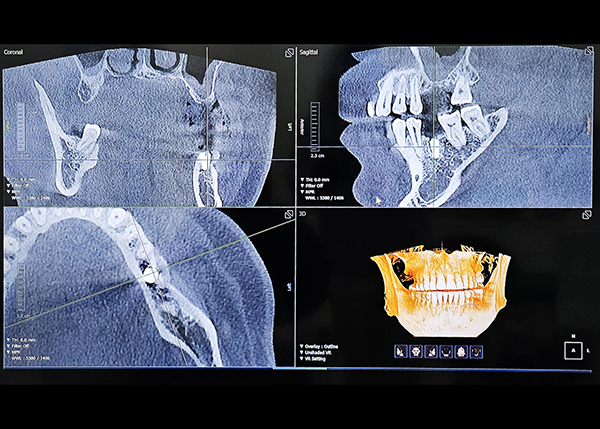

02

디지털 진단과 전문의의 손끝이 만나는 순간,

치료의 정교함이 달라집니다.

성공적인 임플란트 식립을 위해서는 정밀한 진단이 필수적입니다. 3D 스캔·CT·CAD/CAM 기반의 디지털 분석으로 오차를 줄이고, 통합치의학과 전문의 대표원장이 직접 진단·설계·최종 보철까지 전 과정을 담당하여 심미적인 조화와 기능적 안정성을 동시에 고려한 임플란트를 제공합니다.

디지털 정밀 진단

3D CT를 통한 컴퓨터 분석

현재 턱 뼈와 잇몸의 상태를 3차원 입체 영상으로 확인이 가능해

정밀 진단에 따른 오차 없는 수술이 가능